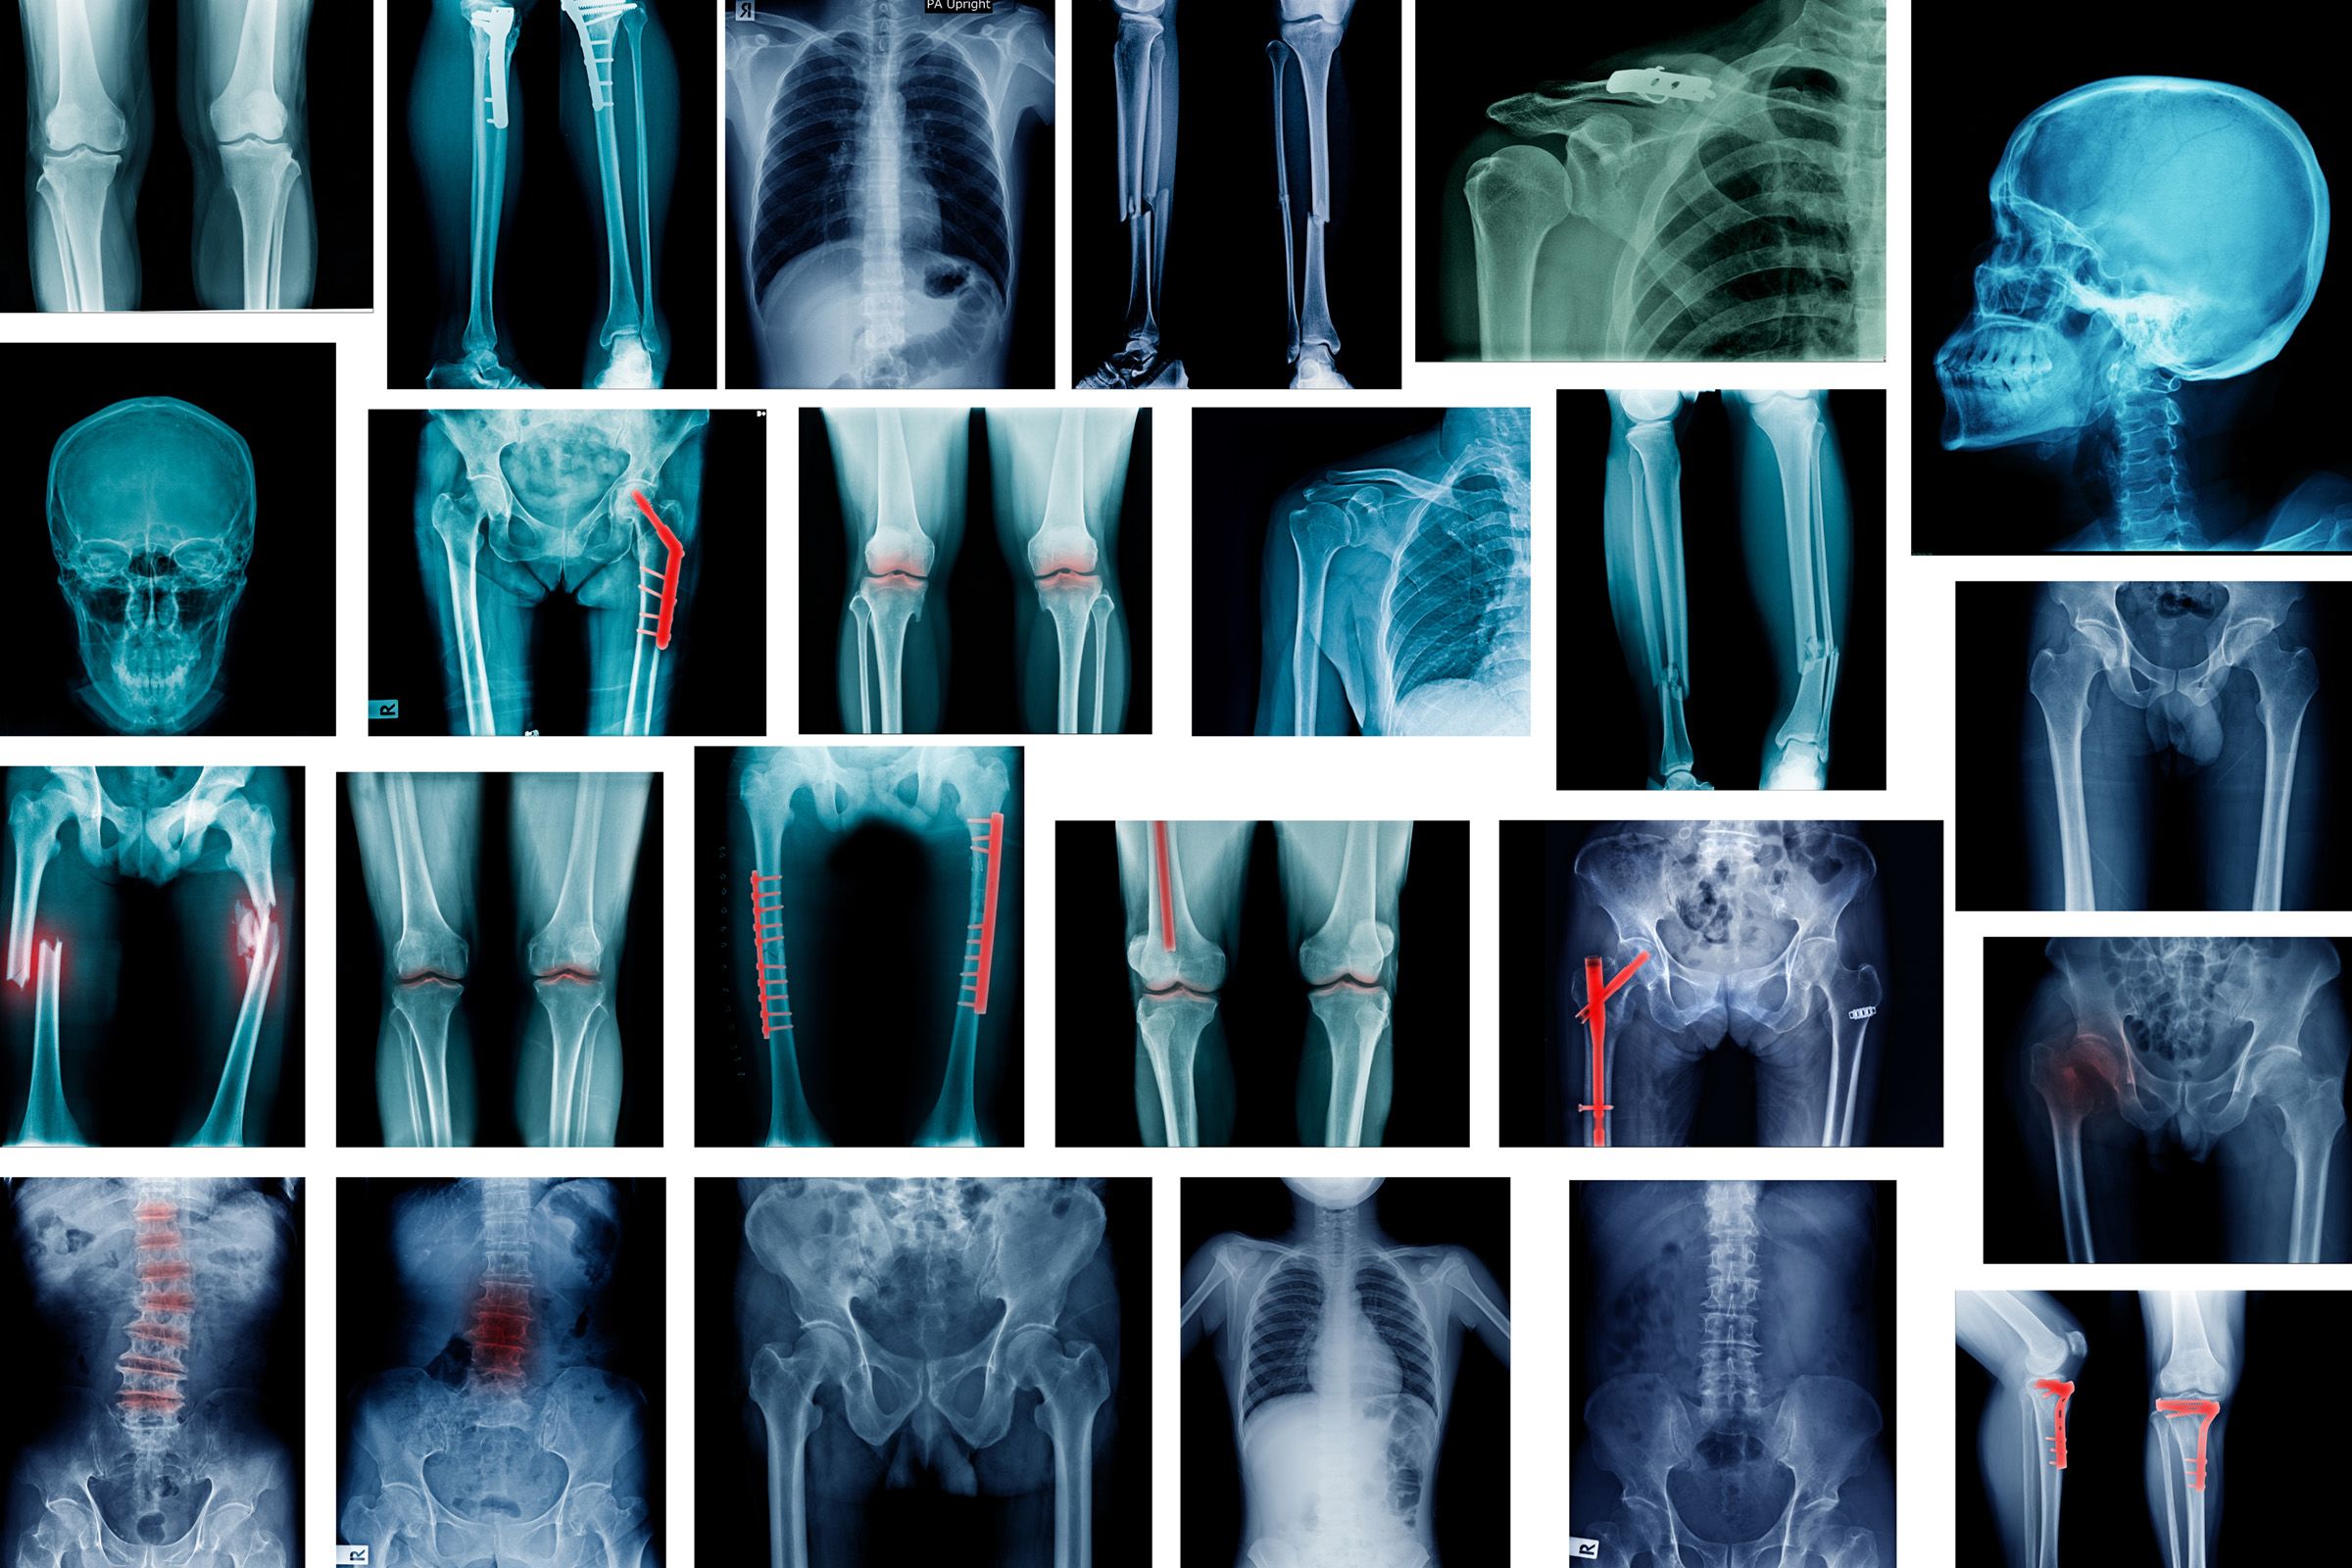

Images such as x-rays, CT/MRI scans and mammograms, and text data including clinicians’ notes, wouldn’t generally be accessible for research in data safe havens due to the risk of potentially identifiable information being present in data releases. Anonymising that kind of information would be too time consuming for large studies.

Interest in using medical images and text data to train artificial intelligence (AI) tools to diagnose disease has expanded rapidly. AI tools could free up clinicians’ time potentially speeding up diagnosis and making it more accessible.

The resulting safe haven is called the Safe Haven Artificial Intelligence Platform (SHAIP), and it has since been used to run exemplar projects in stroke, breast screening, and chest and limb fracture x-rays.